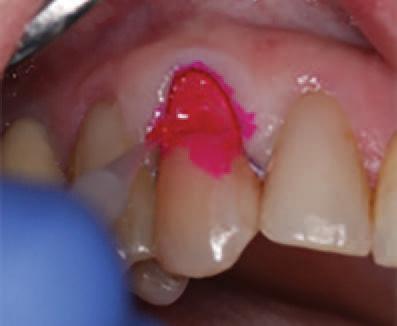

To improve isolation and soft tissue access, a retraction cord was placed before initiating the procedure (Fig. 2). The tooth was evaluated using a caries indicator dye (Kuraray Noritake Dental), helping to identify any remaining infected tissue beneath the dislodged composite (Fig. 3). Decay removal was completed with a diamond bur, and the enamel was bevelled using a starburst pattern to enhance aesthetic blending (Fig. 4). This preparation design was chosen for visual integration rather than bond strength enhancement.

Restoring incisal wear and closing diastema with G-aenial A’CHORD. Courtesy of: Dr Aleksandra Slacan, Poland